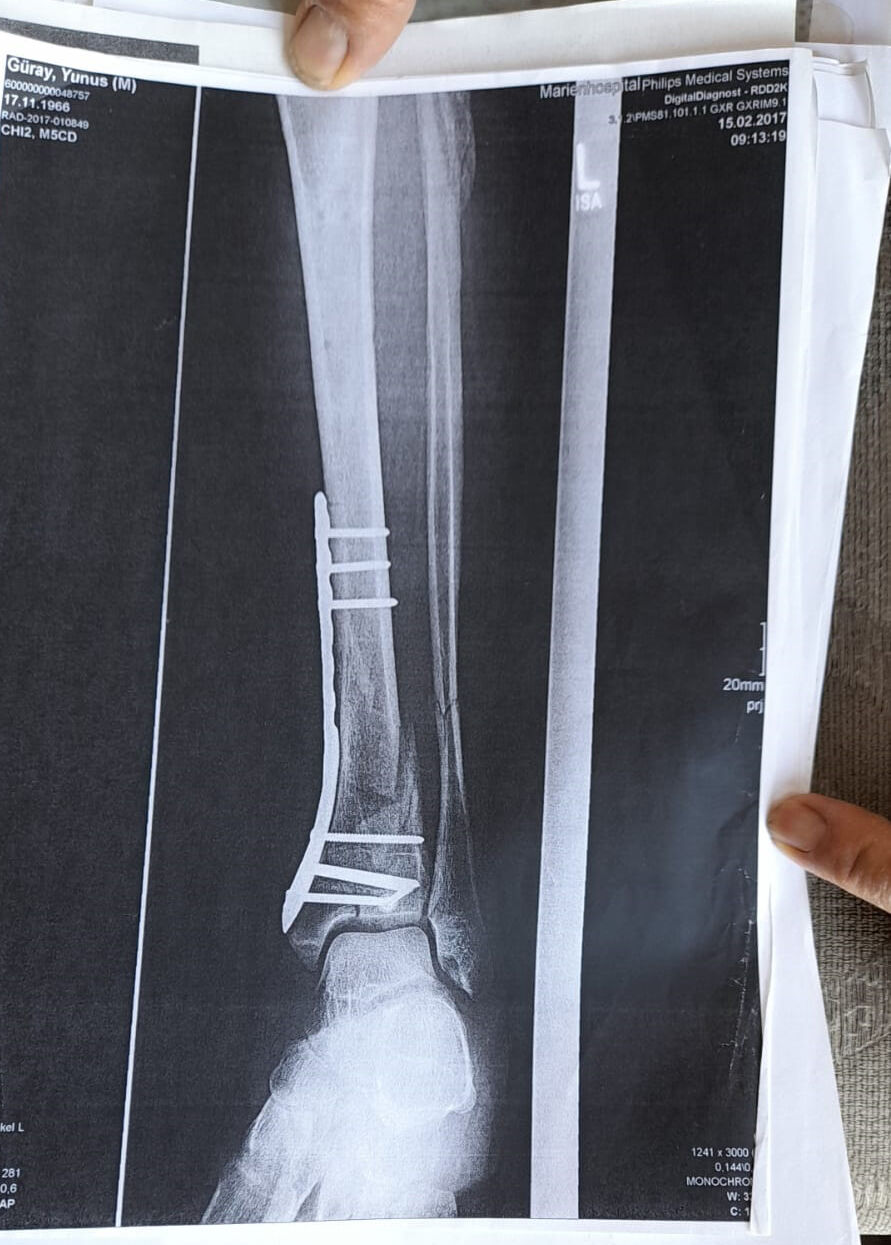

Olay yeriyle ilgili fotoğraf ve görüntüleri mahkemeye sunduklarını kaydeden Güray, 'Ömrümü yediler, demir var ayağımda, sakat bıraktılar. Ayağı keseceklerdi neredeyse. Şu an kalıcı sakatlık var. 1 sene kendime gelemedim, 2 haftada bir ameliyata giriyordum. Almanya'da 3 ay hastanede kaldım ve ayağımda yüzde 3'lük engel oluştu' diye konuştu.

Tazminat miktarını düşük bulan Yunus Güray, şunları söyledi: 'Benim uçak masrafım sadece 22 bin avro tuttu. 9 yıl oldu, bir tane çukur değildi. Adamlar kazmış, kazmış, bırakmış. Tam merkezde bu olay, hani ormanda bir yerde olur, 'Tamam benim de hatam var. Gittim de düştüm' derim. Ama şehrin merkezinde, etrafı çevrili değildi. Yemyeşil alan, gece vaktiydi. Ben mahkemeye verdim, o çukurları 3 ay sonra kapattılar. 6- 7 yerde kazılmış çukurlar vardı. Bir tane değildi. Ayağımda hala demir var. Adil bir karar olmadı.'